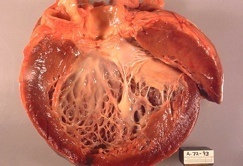

Alteraciones macroscópicas:

- El corazón suele estar agrandado, pesa más y tiene una consistencia blanda, debido a la dilatación de todas las cavidades.

- Los trombos parietales son frecuentes y son una fuente posible de émbolos.

- No existen alteraciones valvulares primarias, y cuando hay insuficiencia mitral (o tricuspídea), se relaciona con la dilatación sufrida por la cavidad ventricular.

Alteraciones histológicas:

- Son inespecíficas y no suelen señalar hacia ningún agente causal concreto.